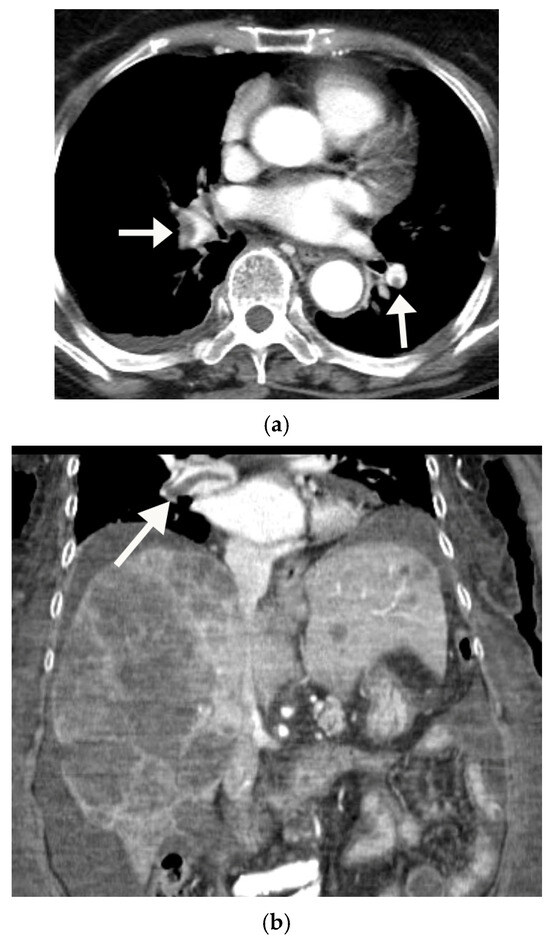

The Middle Meningeal Artery (MMA) occupies a pivotal role in the pathophysiology of migraine, functioning as a vascular and neuroimmune interface that precipitates the characteristic pulsatile pain. The inhibition of this pathophysiological cascade has been investigated as a therapeutic strategy. However, fewer than a dozen centers globally have disseminated procedural or mechanistic data. Given the nascency of this field and the imperative for standardization, the present review synthesizes mechanistic and clinical evidence underpinning intra-arterial pharmacological modulation of the MMA for migraine management. Methods: A focused narrative review was undertaken, drawing upon select but influential studies from pioneering research groups investigating intra-arterial interventions targeting the MMA. The extant literature was thematically categorized and organized according to the loci of cascade interruption and their corresponding clinical outcomes. Results: Since 2009, intra-arterial therapies for severe headache syndromes have evolved, initially utilizing nimodipine for vasospasm-related headaches, progressing to verapamil for reversible cerebral vasoconstriction, and more recently, lidocaine for refractory or status migrainosus, occasionally in conjunction with MMA embolization. Contemporary research uses language that conceptualizes migraine as an immunologically mediated neurovascular disorder, as opposed to a purely vascular or neuronal entity. Recent investigations have identified interleukins such as Interleukin-1β, Tumor Necrosis Factor-α, and Interleukin-6 as critical amplifiers of trigeminovascular activation. Purinergic signaling through the P2X3 receptor and the P2Y13 receptor, in conjunction with pituitary adenylate cyclase-activating polypeptide and vasoactive intestinal peptide pathways, has been implicated in the modulation of MMA excitability and neuropeptide release. The development of novel calcitonin gene-related peptide receptor antagonists, such as zavegepant, further substantiates the artery’s significance as a pharmacological target. Conclusions: These findings support a shift toward immune-modulating intra-arterial therapeutic strategies, with migraine interventions targeting cytokine and neuroimmune signaling within the MMA, rather than relying exclusively on vasodilatory mechanisms.